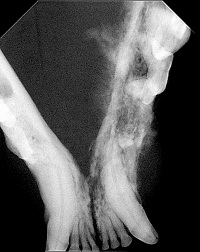

Om een goed beeld van de tumor te krijgen is vaak sedatie nodig. Tijdens deze sedatie kan de uitgebreidheid van de tumor bepaald worden. Tevens kunnen dan, indien nodig, ook röntgenfoto’s van de kaak genomen worden en kunnen histologische biopten genomen worden om de diagnose te bevestigen. De regionale lymfeklieren kunnen nagevoeld worden en aangeprikt worden. Vergroting van de mandibulaire lymfeknopen kan veroorzaakt worden door metastasen, maar zal vaker secundair aan de in de tumor aanwezige ontsteking zijn. Zoals eerder vermeld worden metastasen op afstand, zoals in de longen, zeer zelden aangetroffen omdat de patiënten meestal niet lang genoeg leven om deze te ontwikkelen. Dit maakt het nemen van thoraxfoto’s in het kader van stageren dubieus. In die gevallen, waar een zeer uitgebreide tumor aanwezig is, kan men het nemen van thoraxfoto’s overwegen, maar moet men zich realiseren dat de uitkomst hiervan de therapie zeer waarschijnlijk niet zal beïnvloeden.

Bij orale plaveiselcelcarcinomen kunnen op röntgenfoto’s soms uitgebreide benige veranderingen zichtbaar zijn. Links is de röntgenfoto van de kat van de bovenste afbeeldingen in de inleiding.